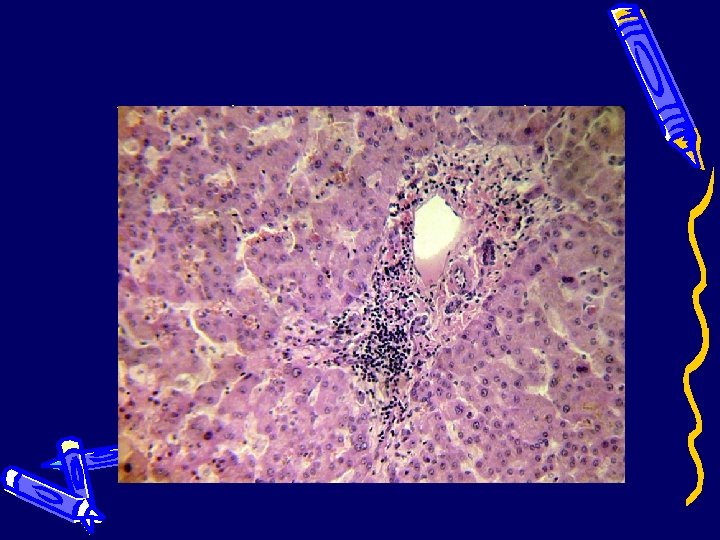

Легкие (смешанная пневмония)

Почки (нефронекроз)

Патологоанатомический диагноз: Основное заболевание (J 10. 0) Грипп А H 1 N 1 c пневмонией: геморрагический трахеобронхит, двухсторонняя полисегментарная серозно-геморрагическая пневмония, положительное вирусологическое исследование материала бронхов методом ПЦР ; отрицательное бактериологическое исследование легких ; пролиферация и накопление клеток типа макрофагов в синусах трахеобронхиальных и мезентериальных лимфатических узлов, красной пульпе селезенки, костном мозге, альвеолах; лимфоидное истощение селезенки, серозногеморрагический катаральный гастроэнтероколит.

Осложнения (R 57. 8) Инфекционно-токсический шок: клинические данные, нефронекроз с развитием острой почечной недостаточности; респираторный дистресс-синдром взрослых, диссеминированное внутрисосудистое свертывание (точечные кровоизлияния в белом веществе полушарий большого мозга, в слизистые оболочки желудочно-кишечного тракта, мочеточников, мочевой пузырь,